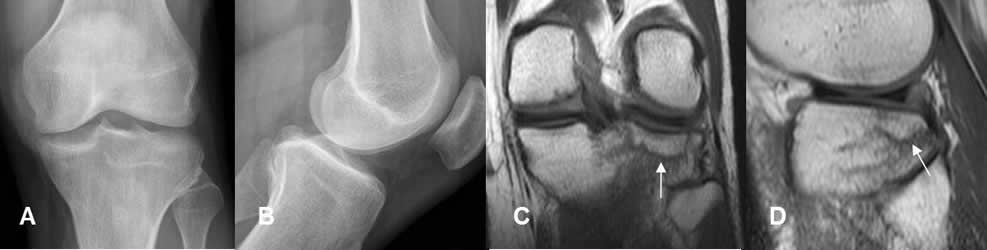

Fig 23 B. Trauma oculto.

A: Rx AP y B: Rx lateral. Paciente con trauma directo, donde no se encuentran alteraciones.

C: RM coronal en T1 y D: RM sagital en T1. Edema óseo del platillo tibial lateral, con fisura no deprimida.